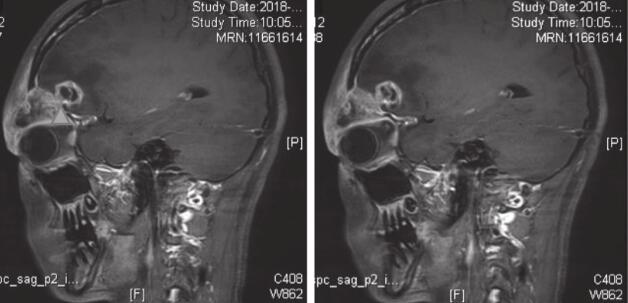

入院后2018年2月8日起予以头孢曲松2.0 g静脉滴注每12小时一次+甲硝唑0.5g静脉滴注每12小时一次治疗。同时联系相关科室取病理明确诊断。2018年2月9日眼科会诊指出:患者眼部大部分病灶在球后,不易活检,眼球前部病灶存在穿刺后伤口不易愈合风险,建议行脑穿刺活检。2018年2月8日及2018年2月11日先后两次出现发热,并感头痛,加用20%甘露醇125ml静脉滴注每12小时一次降颅压治疗,头痛缓解。2018年2月13日转神经外科行全麻下病变组织活检术,术中取右侧眉弓切口进入,切开肌肉后见病灶,灰红色,疏松,血供一般,质地软,病灶向深部侵犯骨质,取部分病变组织送冷冻,提示(眶上皮下)大量以中性粒细胞为主的炎性细胞浸润,伴类上皮反应,及朗格汉斯样多核巨细胞反应。再取部分病变组织送病理,培养及二代测序等。2018年2月14日转回抗生素研究所病房,再次出现发热、头痛,考虑手术后发热,需兼顾院内感染相关细菌;2018年2月16日调整抗感染方案:停用上述抗生素,换用哌拉西林/他唑巴坦4.5g每8小时一次,并将20%甘露醇125ml加量至每8小时一次降颅压治疗,患者体温逐渐下降;2018年2月20日体温平,头痛逐渐缓解,右侧眼睑皮肤红肿逐渐改善,略能睁眼,病情好转。期间血、脑脊液、手术活检组织培养均回报阴性,术中标本病原学二代测序阴性。术后2018年2月26日复查MRI(图3):右侧眶上外侧壁及周围软组织水肿略有吸收,右额异常强化灶略有增大。2018年2月26日手术病理结果:(右侧眶上皮下)朗格汉斯组织细胞增生症。故2018年2月26日起停抗感染治疗。

图3 术后2周复查MRI

右侧眶上外侧壁及周围软组织水肿略有吸收,右额异常强化灶略有增大